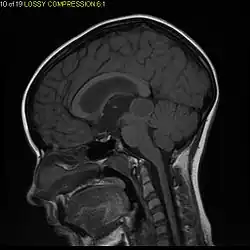

Usually – depending on the interview of the patient and after a clinical exam which includes a neurological exam and an ophthalmological exam – a CT scan and/or an MRI scan will be performed to confirm the presence of a tumor. They are usually easily distinguishable from normal brain structures using these imaging techniques. A special dye may be injected into a vein before these scans to provide contrast and make tumors easier to identify. Pilocytic astrocytomas are typically clearly visible on such scans, but it is often difficult to say based on imaging alone what type of tumor is present.

Pilocytic astrocytomas are often cystic tumors, and, if solid, tend to be well-circumscribed.